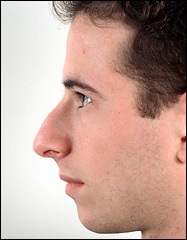

A fénykép a bal oldalon mutatja egy ember tipikus megnövekedett nazális gerinc. Ez jelentősen növeli az orrát előre. A fénykép után a művelet ugyanaz az ember nagyon jól néz ki.